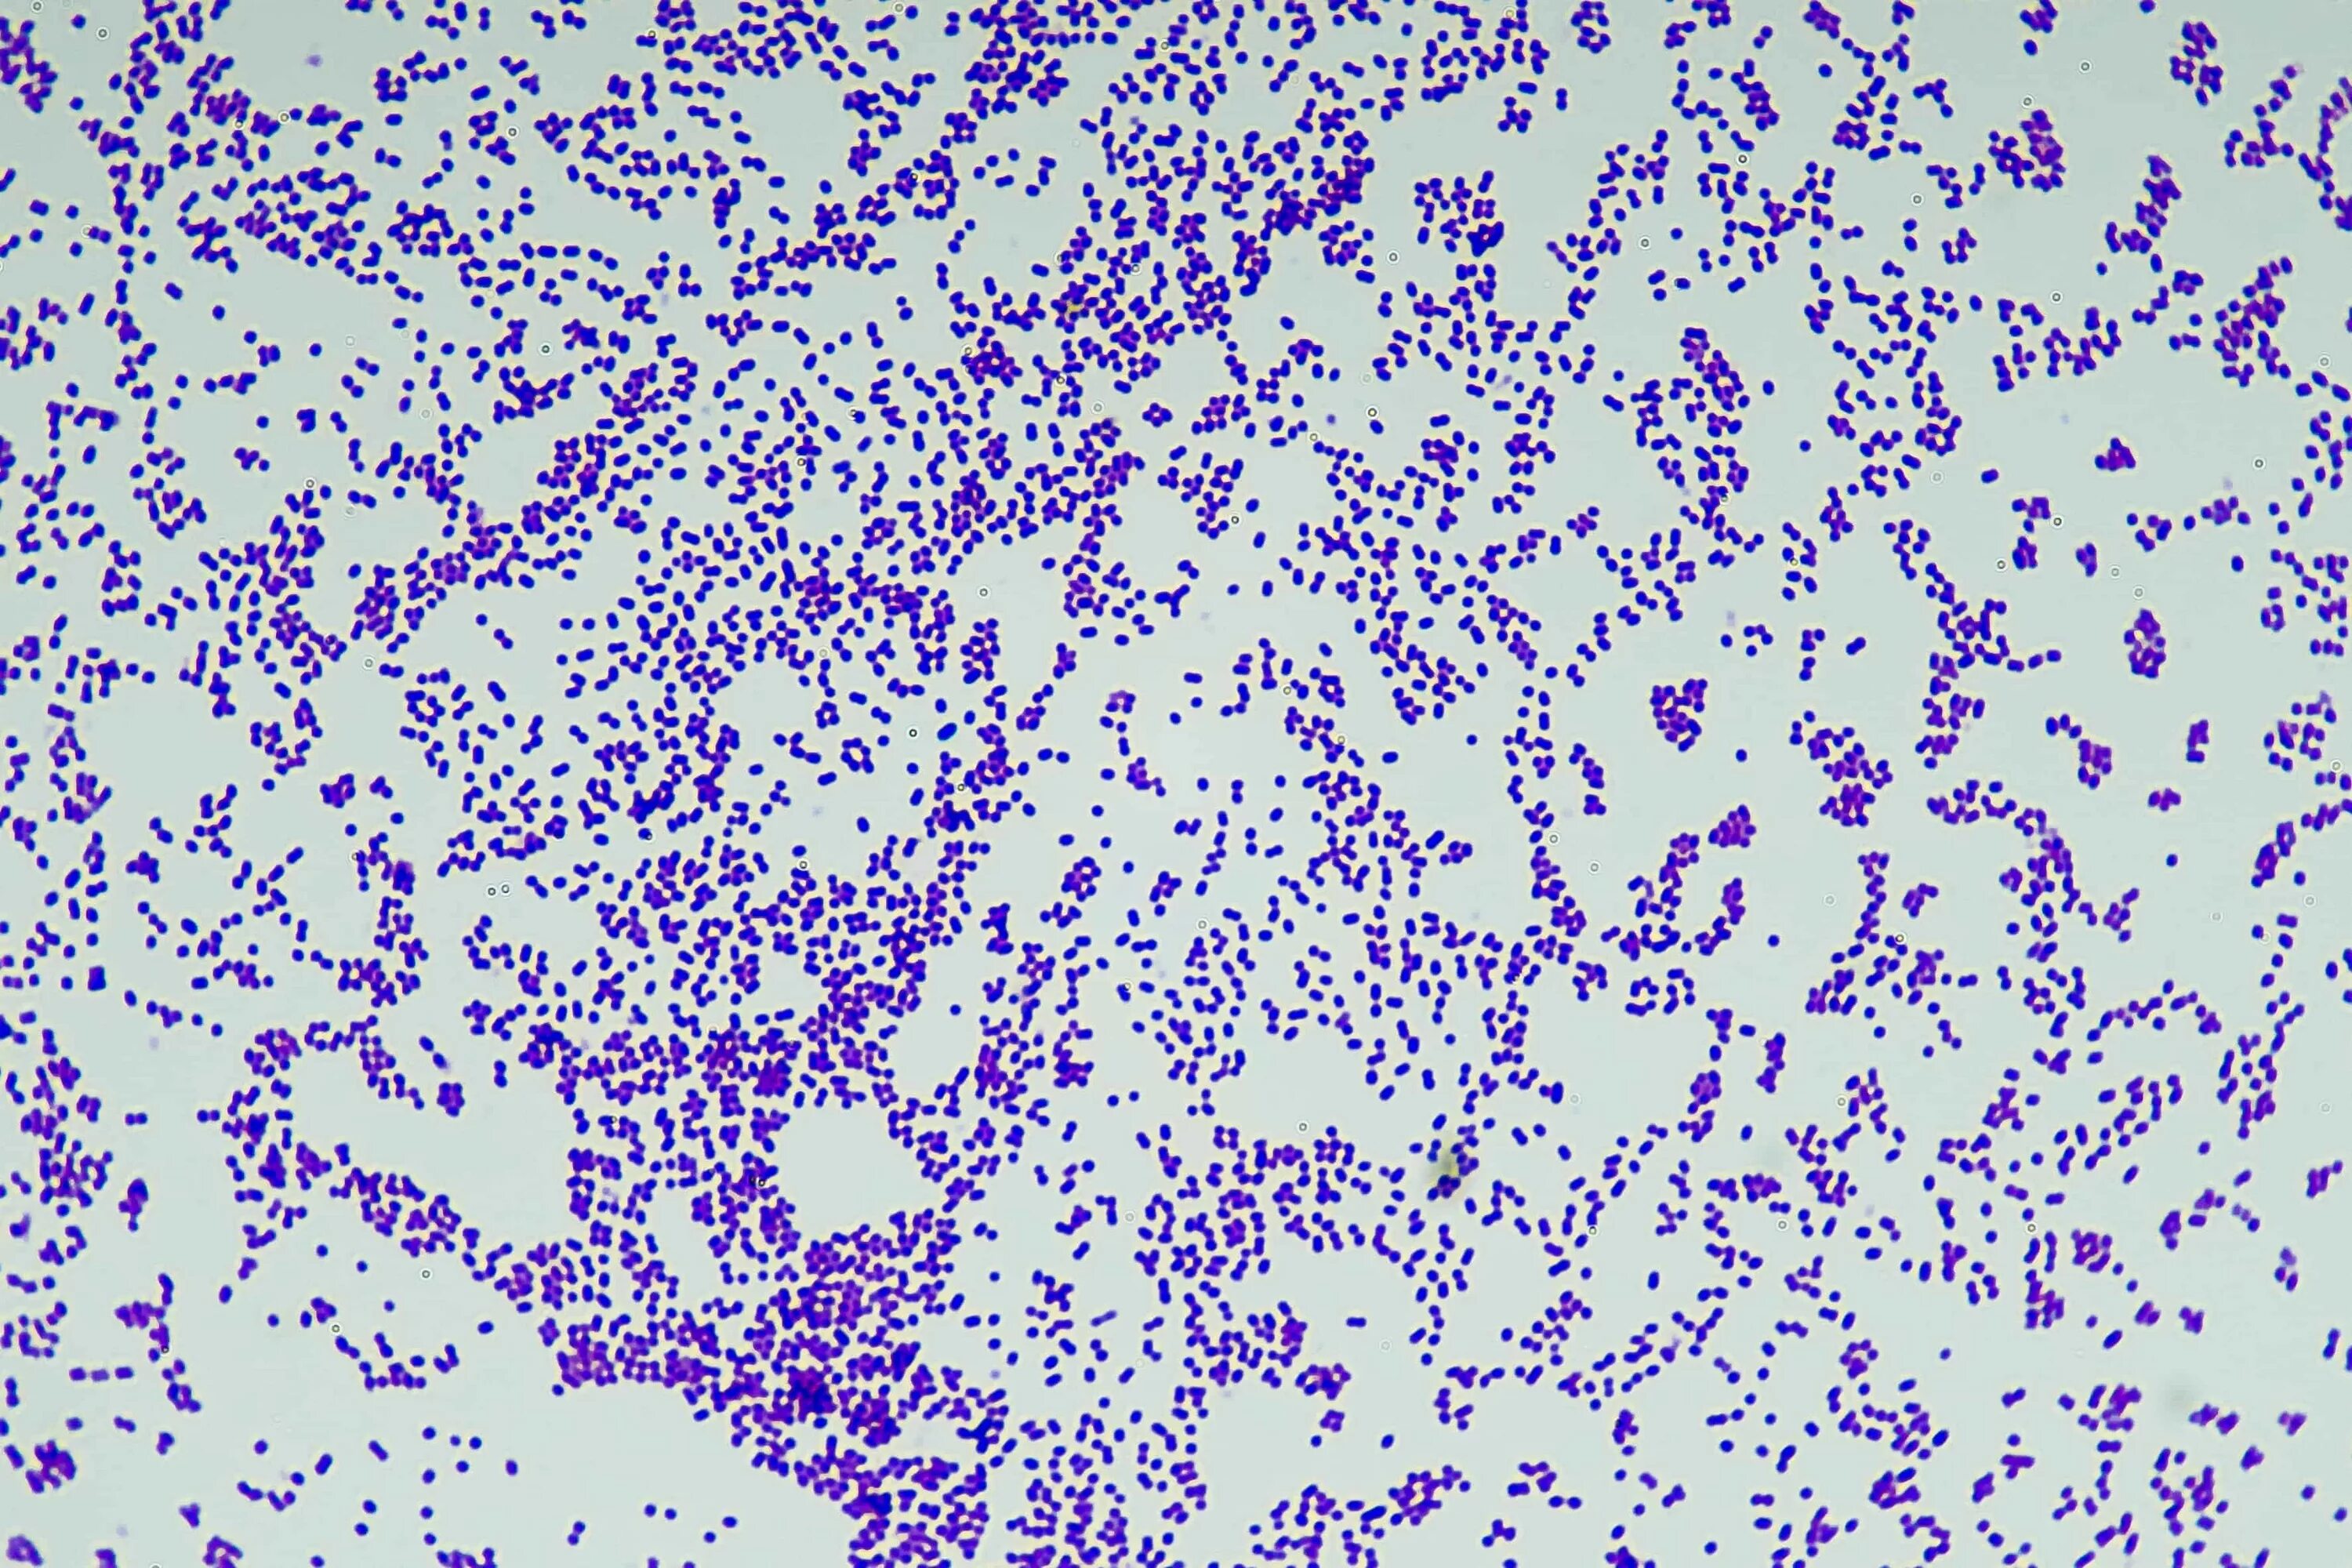

Анализ мазка микрофлора кокки. кокко-бациллярная микрофлора в мазке у женщин.Микрофлора коккобациллярная что это у женщинМикрофлора коккобациллярная что это у женщинГрамположительные палочки в анализе. микрофлора мазка у женщин. грамм положительные палочки в мазке норма?.Микрофлора коккобациллярная что это у женщинАнализ мазка микрофлора кокки. норма кокков в мазке. грамотрицательные кокки в мазке у женщин.Микрофлора коккобациллярная что это у женщинМикрофлора коккобациллярная что это у женщинМикрофлора коккобациллярная что это у женщинМикрофлора коккобациллярная что это у женщинАнализ мазка микрофлора кокки. анализ микрофлоры коккобациллярная. микрофлора палочки кокки мазок норма.Микроскопическое исследование отделяемого уретры. исследование мазков отделяемого мочеполовых органов. коккобациллярная микрофлора.Лептотрикс в мазке на флору. мазок на степень чистоты. коккобациллы у женщины в мазке на флору.Бациллярная умеренная. бациллярная микрофлора.Микрофлора коккобациллярная что это у женщинМикрофлора коккобациллярная что это у женщинМикрофлора коккобациллярная что это у женщинНорма грамм(+) кокки в мазке на флору. норма кокков в мазке. грамотрицательные кокки в мазке у женщин.Микрофлора коккобациллярная что это у женщинМазок на флору бациллярная. бациллярная микрофлора в мазке.Исследование гинекологического мазка норма. анализ мазка микрофлора кокки.Микрофлора мазка у женщин.Норма грамм(+) кокки в мазке на флору. микрофлора смешанная скудная.Мазок на флору норма палочки. анализ мазка микрофлора кокки. микрофлора палочки в мазке у мужчин.Микрофлора коккобациллярная что это у женщинСмешанная микрофлора. грамвариабельные бациллы. грамвариабельные это.Микрофлора коккобациллярная что это у женщинМикрофлора коккобациллярная что это у женщинМикрофлора коккобациллярная что это у женщинМикрофлора коккобациллярная что это у женщинМикрофлора коккобациллярная что это у женщинМикрофлора коккобациллярная что это у женщинМикрофлора коккобациллярная что это у женщинМикрофлора коккобациллярная что это у женщинМикрофлора коккобациллярная что это у женщинМикрофлора коккобациллярная что это у женщинМикрофлора коккобациллярная что это у женщинМикрофлора коккобациллярная что это у женщинПсевдомицелий кандида. грибы candida псевдомицелий. коккобациллярная форма.Микрофлора коккобациллярная что это у женщинМикрофлора коккобациллярная что это у женщинМикрофлора коккобациллярная что это у женщинЛептотрикс кокки. коккобациллы микроскопия. грамвариабельная коккобациллярная.Микрофлора коккобациллярная что это у женщинМикрофлора коккобациллярная что это у женщинМикрофлора коккобациллярная что это у женщинМикрофлора коккобациллярная что это у женщинКоккобациллярная микрофлора. коккобациллярная микрофлора в мазке у женщин.Микрофлора палочки кокки мазок норма. анализ мазка микрофлора кокки. исследование мазков отделяемого мочеполовых органов.Микрофлора коккобациллярная что это у женщинМикрофлора коккобациллярная что это у женщинМикрофлора коккобациллярная что это у женщинМикрофлора коккобациллярная что это у женщинМикроскопическое исследование мазка у женщин. анализ на микрофлору. палочки умеренно в мазке.Микрофлора коккобациллярная что это у женщинМикрофлора коккобациллярная что это у женщинМикрофлора коккобациллярная что это у женщинНорма кокков в мазке. кокковая микрофлора в мазке.Микрофлора коккобациллярная что это у женщинМикрофлора коккобациллярная что это у женщинМазок на флору у женщин норма палочки.Кокковая микрофлора в мазке. норма грамм(+) кокки в мазке на флору.Микрофлора коккобациллярная что это у женщинАнализ мазка микрофлора кокки. норма кокков в мазке.Микрофлора коккобациллярная что это у женщинГрам палочки в мазке. микрофлора грамм + палочки в большом количестве. грам кокки в мазке у женщин.Микрофлора коккобациллярная что это у женщинМикрофлора коккобациллярная что это у женщинМикрофлора коккобациллярная что это у женщинМикрофлора коккобациллярная что это у женщинМикрофлора коккобациллярная что это у женщинЭпителий из уретры у женщин норма таблица. лейкоциты в поле зрения в мазке у женщин норма. анализ на эпителий кошки расшифровка. эпителий умеренное количество в мазке у женщин что это.